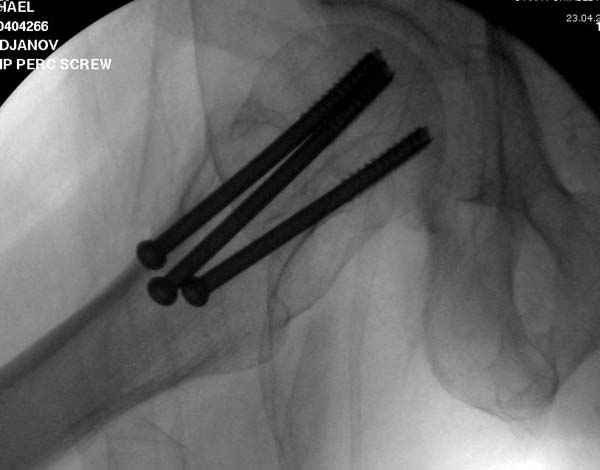

Наверное речь идет насчет parallel guide из набора. Применяем по возможности всегда, но,

как видно на снимке, не всегда получается

паралельно.

Такие несмещенные переломы обычно для молодых резидентов, и бывают технические неточности, но в этом случае посчитали фиксацию адекватной.